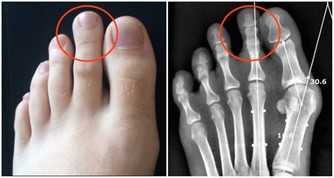

排除其他疾病。很多如腫瘤、結核、甲狀腺功能亢進症等疾病都會導致體重下降,而我提到的三種疾病都容易與糖尿病伴發而行,所以如果明顯的體重下降,首先要篩查這三種疾病,如果有隱匿的疾病沒有發現,那麼任何阻止體重減少的治療都是治標而不治本的。